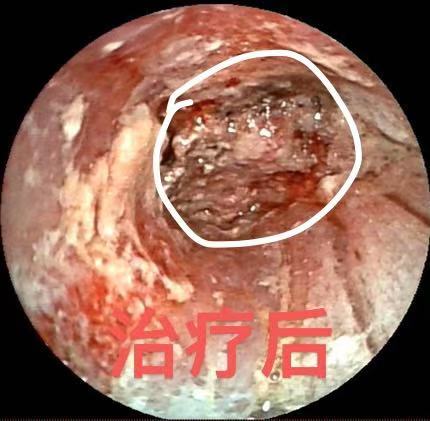

治疗后

面对这一治疗难题,呼吸与危重症医学科二病区主任屈东明博士组织科室介入诊疗团队进行了充分的术前评估和讨论,决定为陈先生实施支气管镜下化学消融治疗。在手术中,诊疗团队使用特制注射穿刺针,对管腔内肿瘤组织多点注射甲苯磺酰胺注射液(PTS)。手术过程顺利,术后肿瘤组织坏死脱落,被阻塞的气道明显畅通,陈先生的临床症状得到了部分改善。